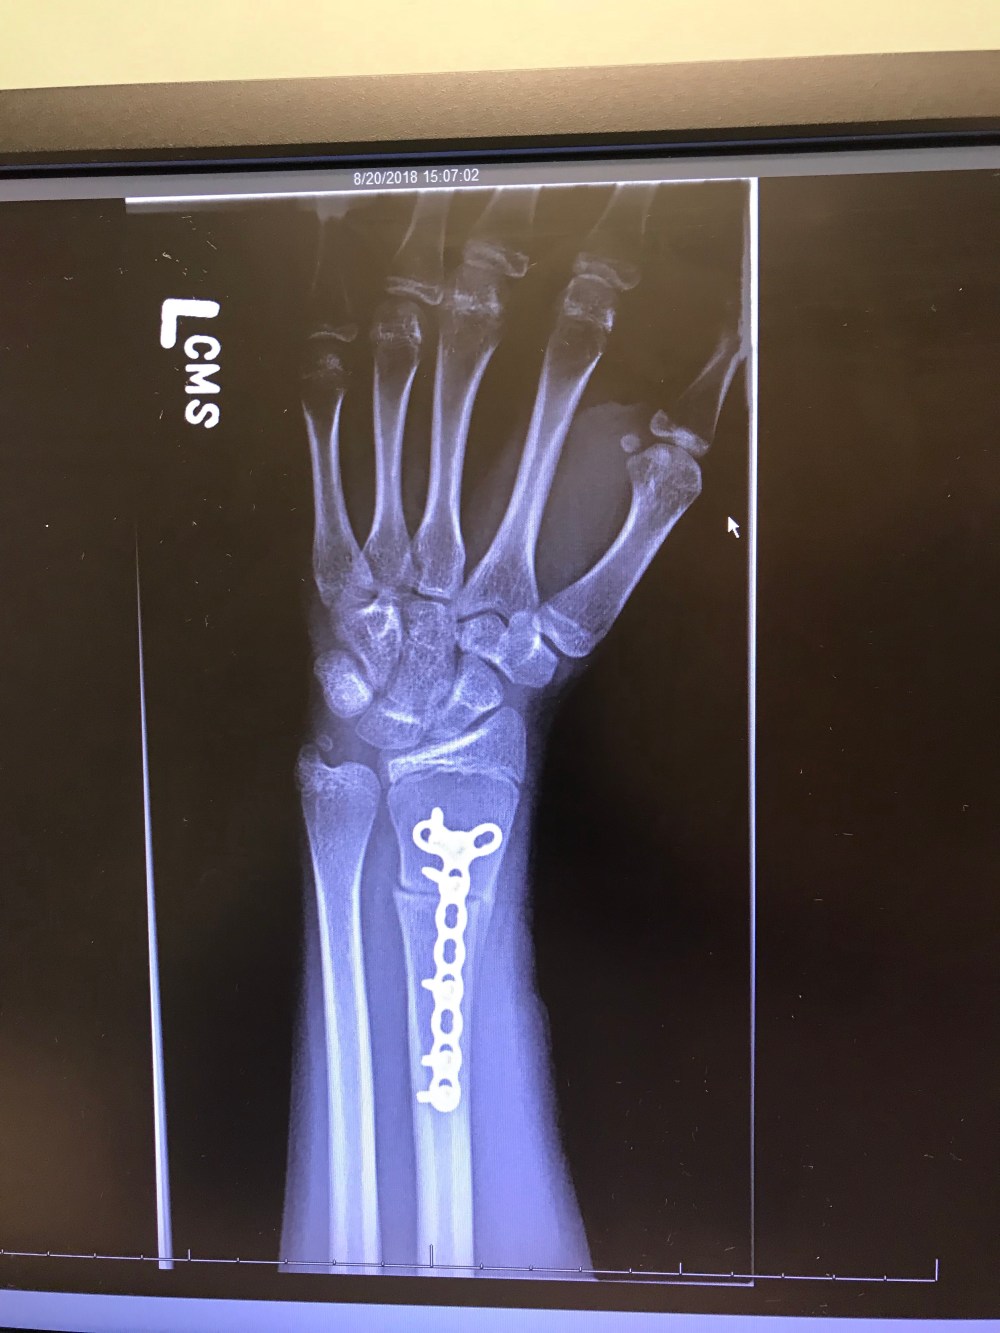

Her doctor referred her to a surgeon who said the after the original injury, the broken radius bone had healed with a curve, and the curved bone was pushing the ulna out of place when Lauren would rotate her wrist. The only way to fix it was to cut the radius and realign the bone properly with a metal plate, and repair the damaged ligaments. Surgery was scheduled July 3. She was in a soft cast to allow swelling up past her elbow, and she was hurting pretty bad for days. You don’t mess around with hydrocodone, but she took that for several days and still hurt anyway. Her hard cast stopped before her elbow and gave her more range of motion than the soft one, and she lived with that until August 20.